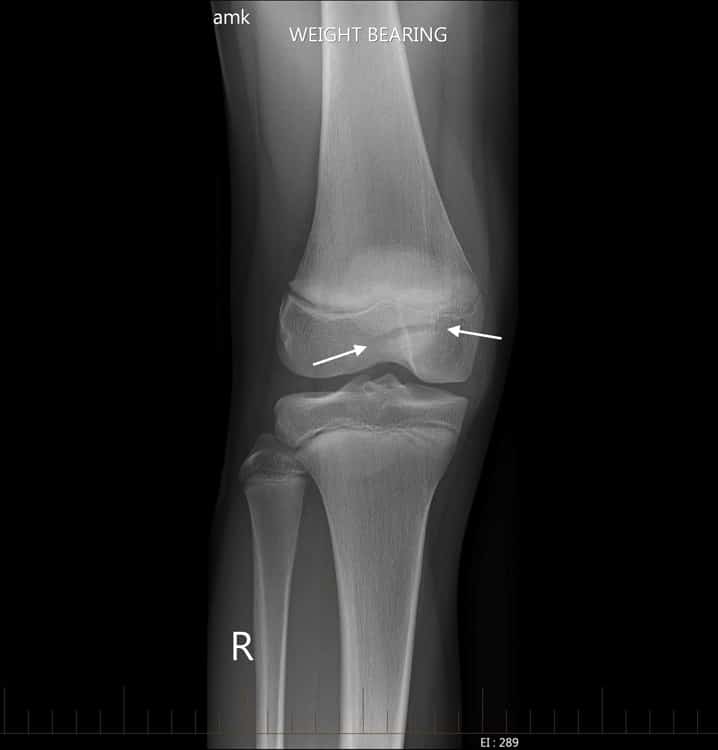

Xương bánh chè 2 mảnh

» Thông tin: Nam giới – 14 tuổi.

» Lâm sàng: Đau khớp gối.